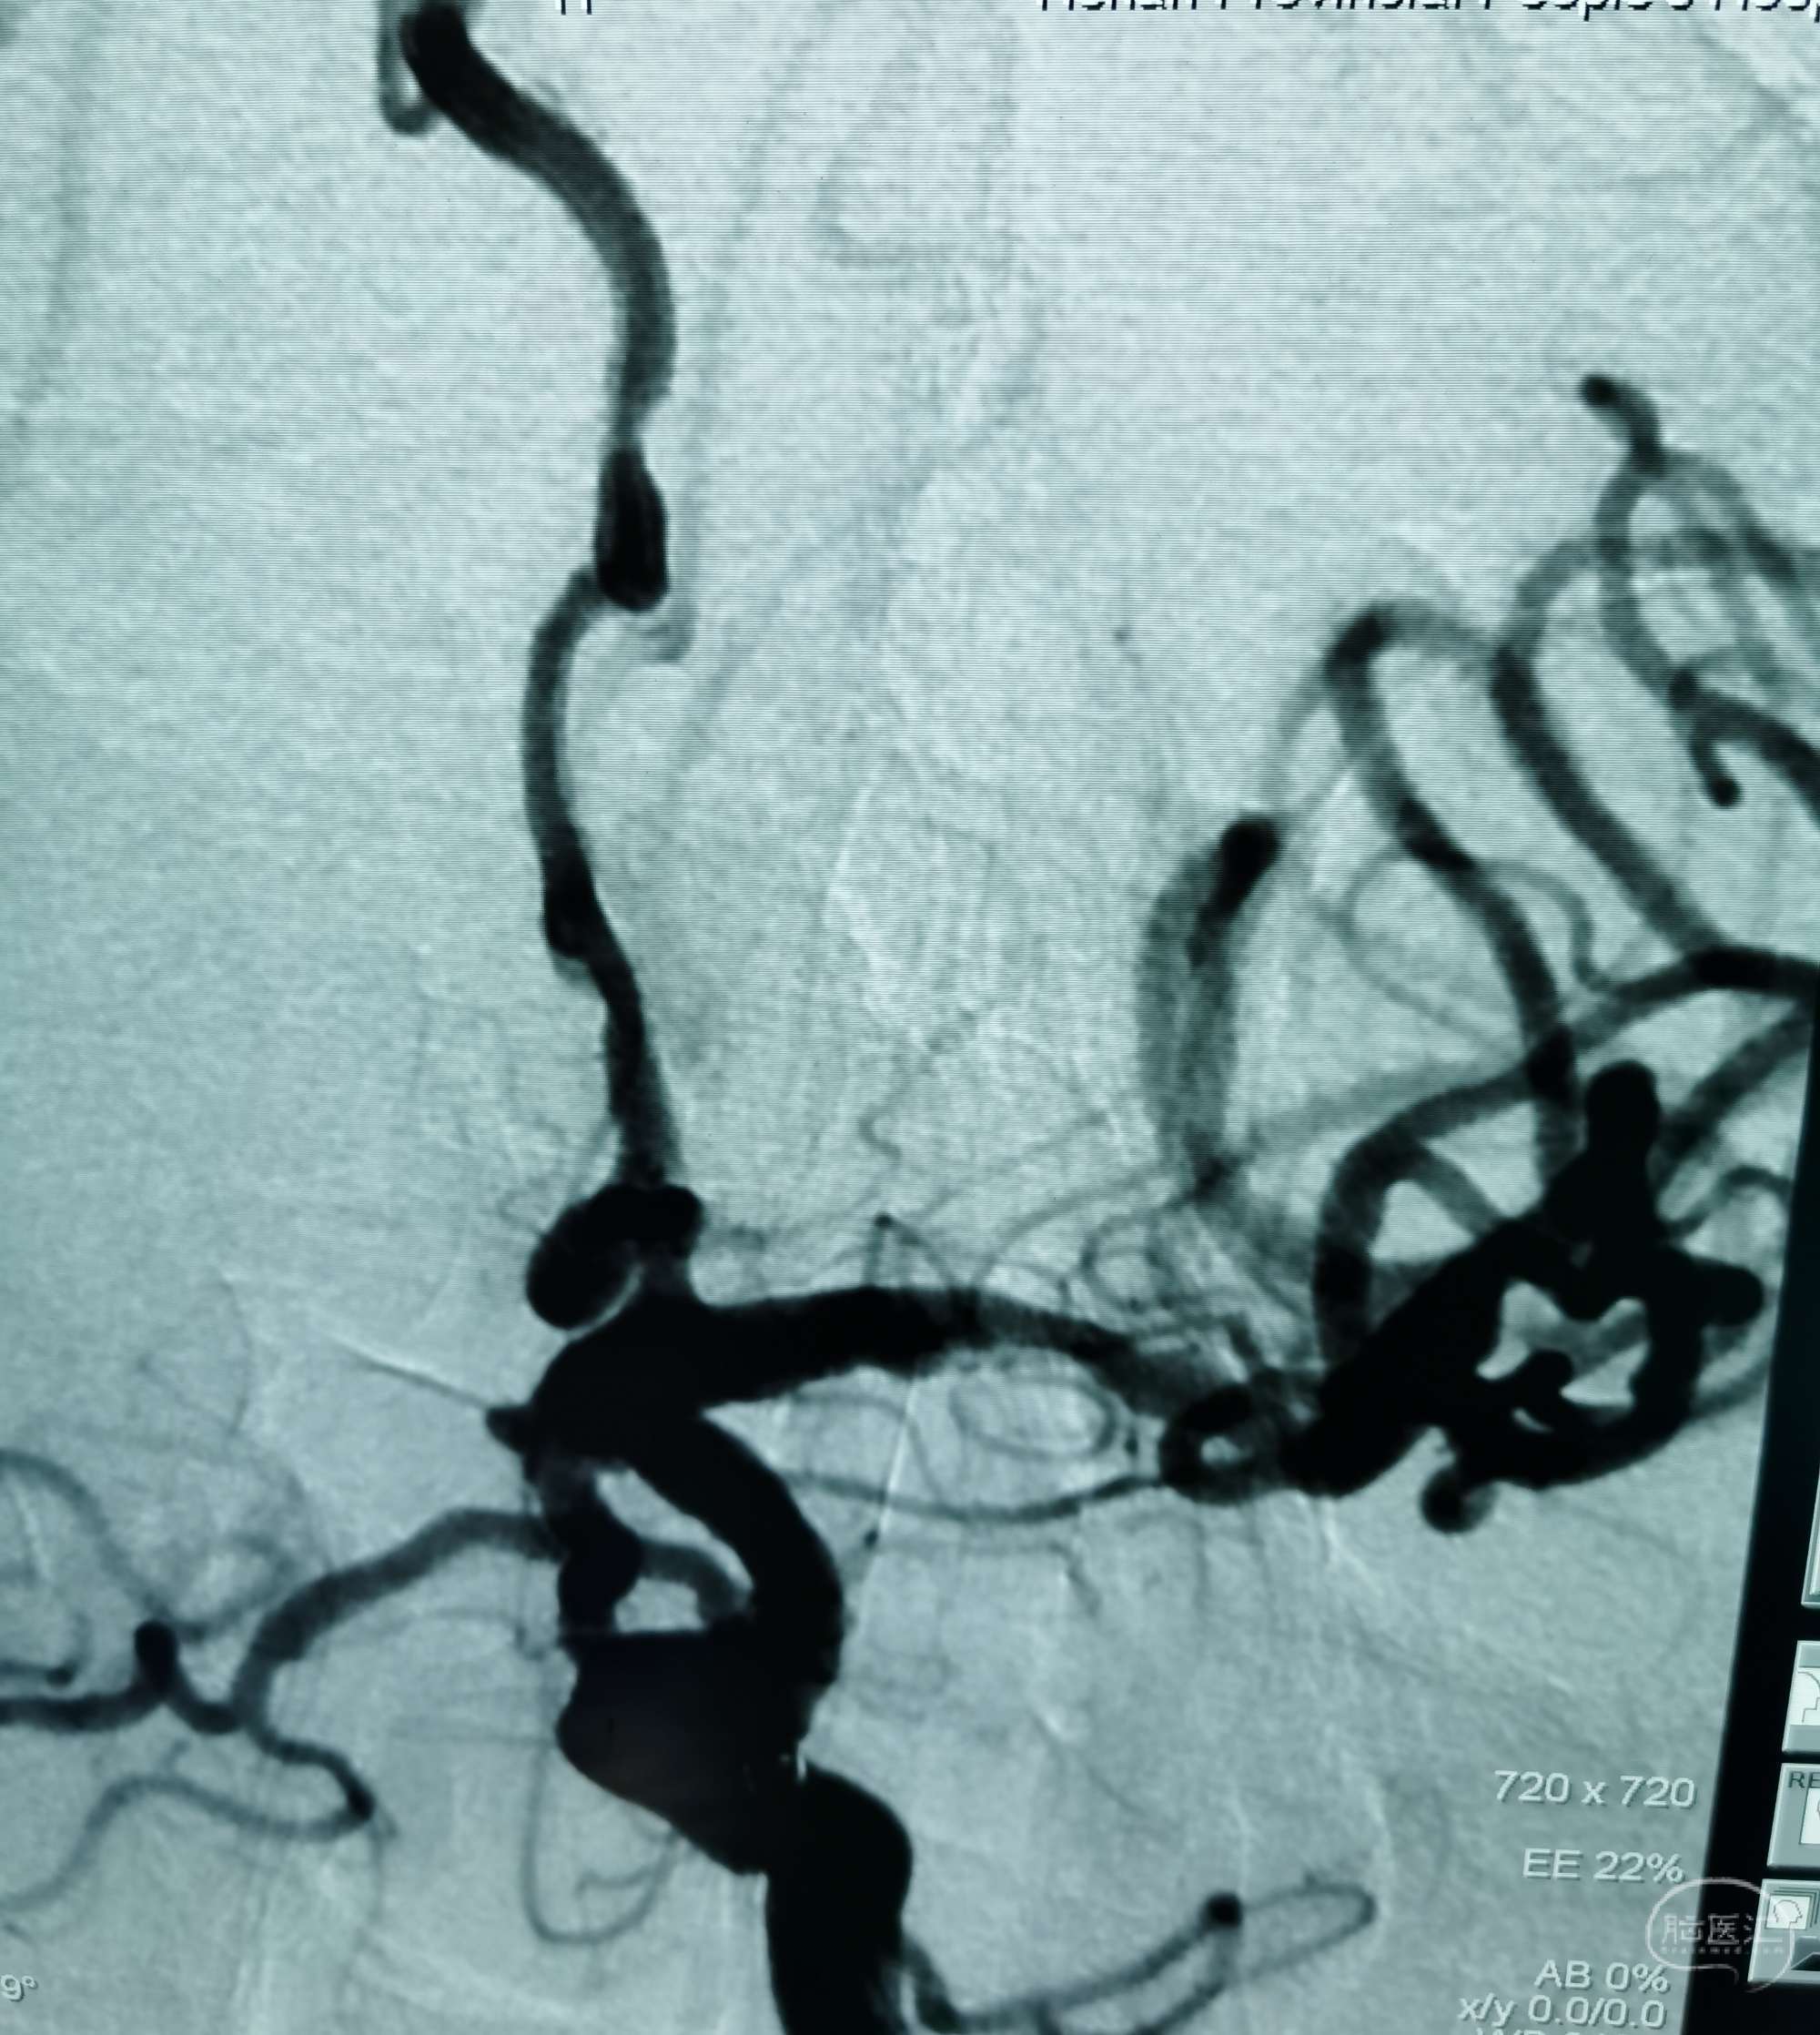

DSA示左侧后交通微小动脉瘤,起自后交通,血泡样。

胚胎型后交通动脉。

压颈DSA造影示左侧P1缺如。